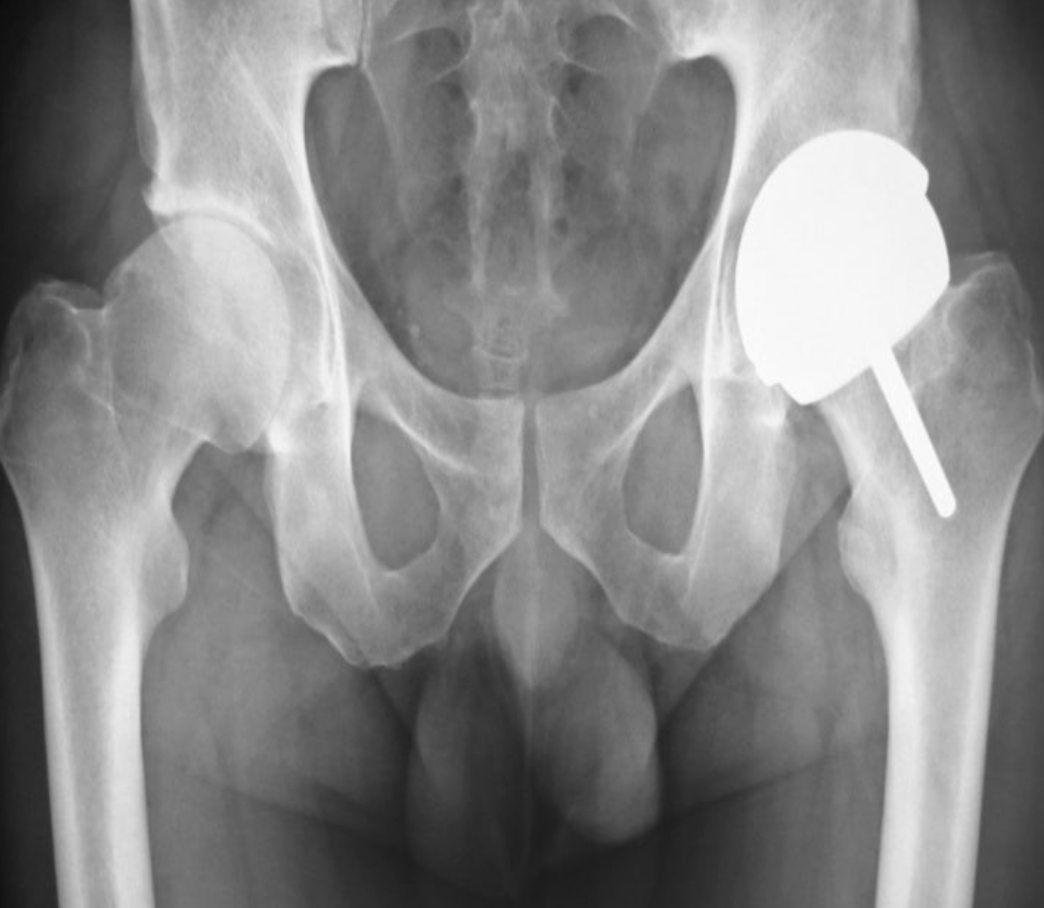

Dr. Sílvio Dias

Ortopedia geral e traumatologia